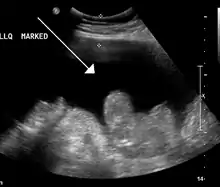

Ultrasound investigation is often performed prior to attempts to remove fluid from the abdomen. This may reveal the size and shape of the abdominal organs, and Doppler studies may show the direction of flow in the portal vein, as well as detecting Budd-Chiari syndrome (thrombosis of the hepatic vein) and portal vein thrombosis. Additionally, the sonographer can make an estimation of the amount of ascitic fluid, and difficult-to-drain ascites may be drained under ultrasound guidance. An abdominal CT scan is a more accurate alternate to reveal abdominal organ structure and morphology.